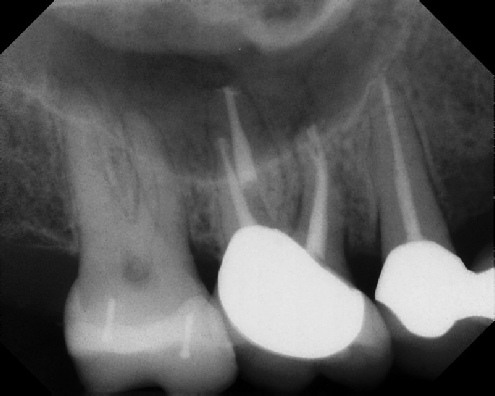

Root Canal Retreatment - Meriden 8 mos. recall Post-op Pre-op